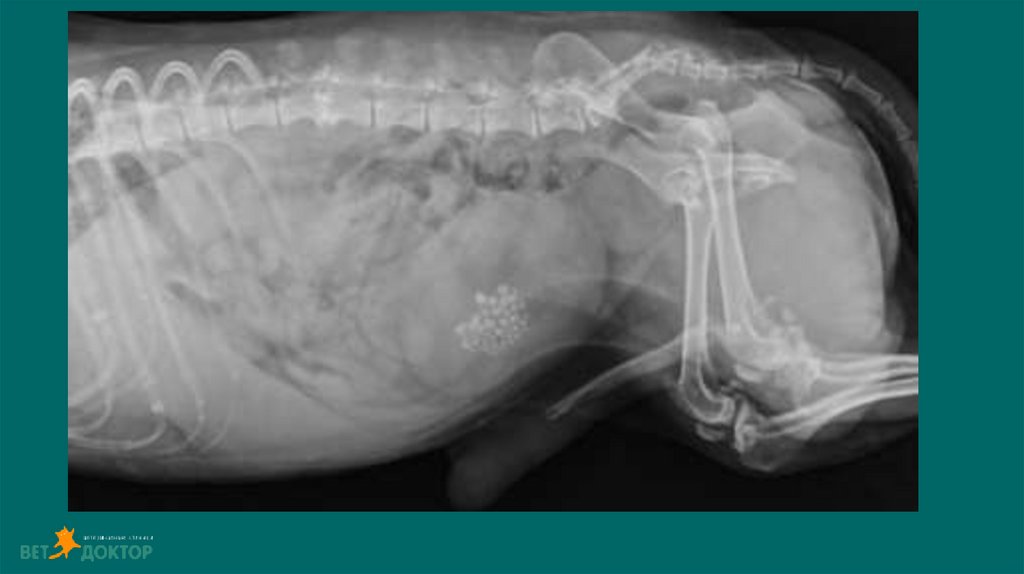

Размер и симметричность почек, размер и топографию мочевого пузыря, размер и

положение репродуктивных органов.

У собак почки имеют бобовидную форму. Размер в 2,5-3,5 раза превышают длину L 2

У кошек овальная до круглой. Размер почек измеряют на ВД проекции в 2,4-3,0 раза

превышают длину L2

Размер проксимального отдела мочеточника :

Собаки 2-3мм. Кошки 1-2мм

Метод выявления рентгеноконтрастных уролитов (фосфат кальция, оксалат кальция,

струвиты)

Ураты /цистеиновые уролиты рентгенопрозрачны.